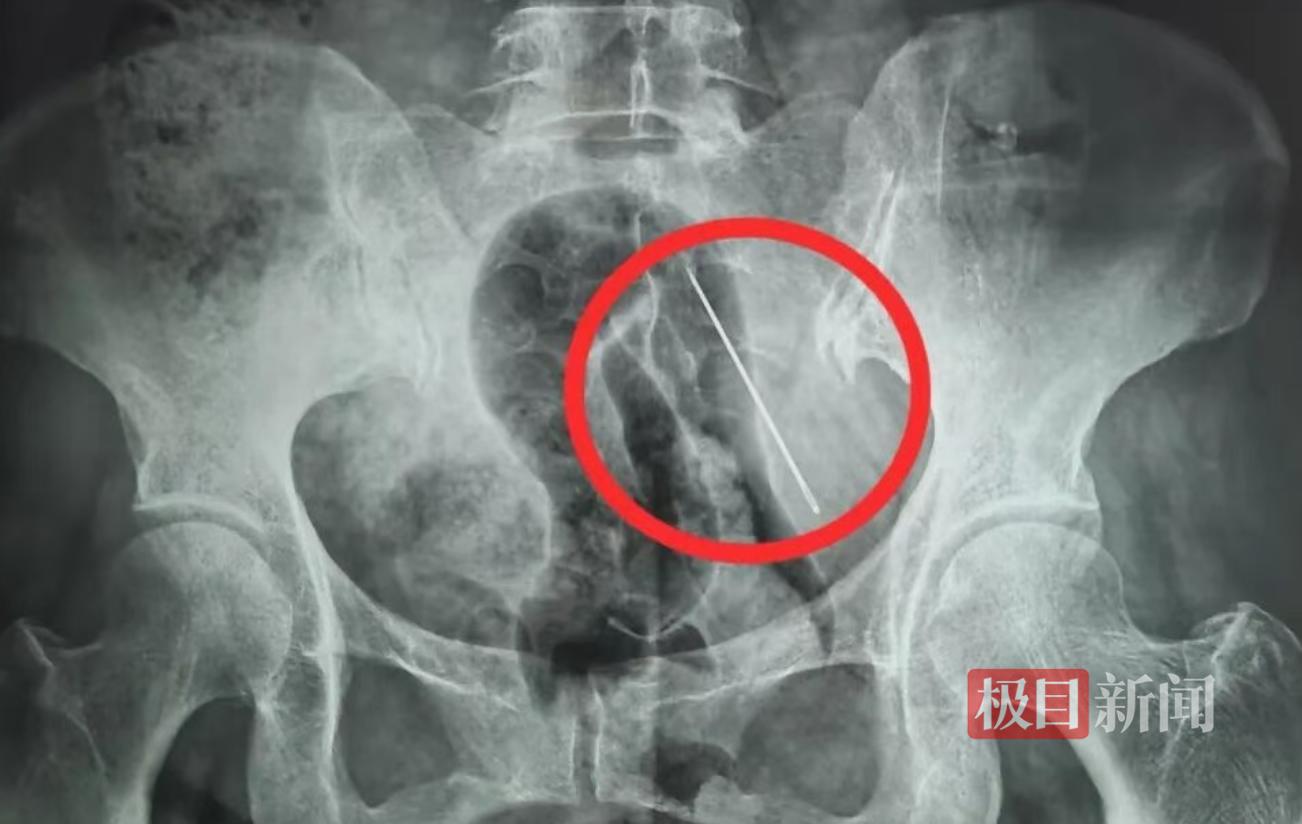

X光片显示张某腹部内有异物(医院供图)

接诊后,急诊科当即安排张某进行腹部CT和X线检查。检查结果显示,她的腹壁内有一根长4厘米的异物。经研判,这根缝衣针只是扎入脂肪层内,并未穿透掉入腹腔。